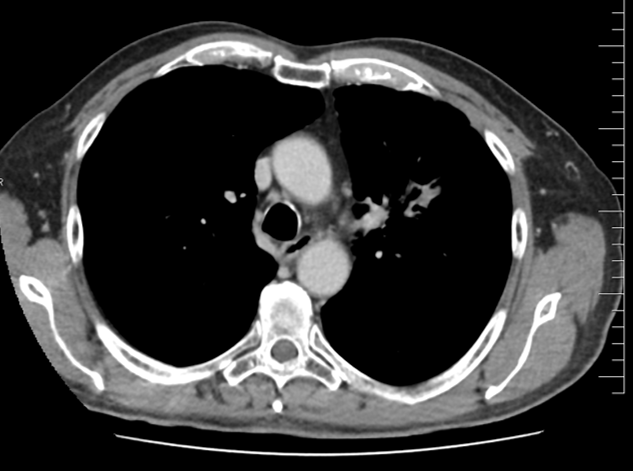

Do druhé linie léčby byl zvolen pembrolizumab. Léčba byla zahájena v 10/2021 a byla velmi dobře tolerována. Pacient si stěžoval pouze na mírnou únavu. Na prvním kontrolmím přešetření v 1/2022 byla popsána výrazná regrese metastatického postižení plic. Léčba pokračovala bez komplikací, na dalších přešetřeních až do 8/2022 popsána pokračující regrese plicního postižení. Od 11/2022 se jednalo již o stabilizaci reziduálního plicního postižení. Léčba pembrolizumabem pokračovala po dobu 2 let do 9/2023 a v současné době trvá téměř kompletní remise nemoci.

Řez plicemi z CT screeningu: Kontrolní  CT plic po 2 sériích léčby pembrolizumabem v 1/2022.

Obr 3. – Kontrolní  CT plic po 2 sériích léčby pembrolizumabem v 1/2022.